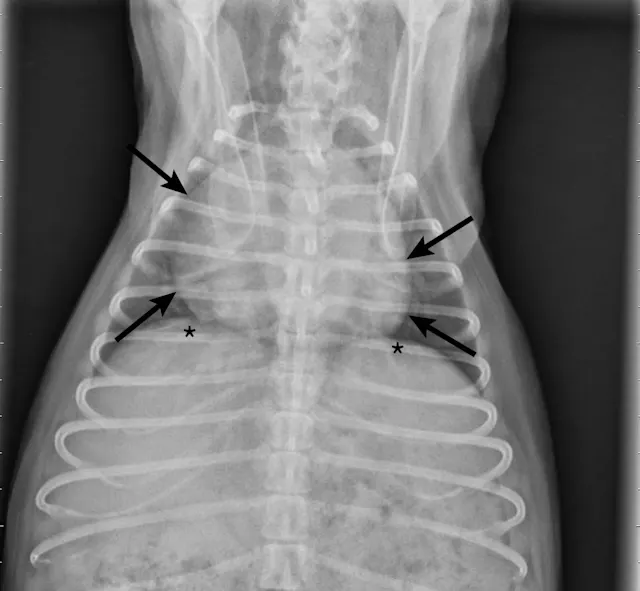

On examination, the dog was panting with expiratory effort and crackles auscultated diffusely. She exhibited an occasional goose-honking cough and retch. Her body temperature was normal. Radiography (Figures 1 and 2), fluoroscopy (Figure 3), and bronchoscopy (Figures 4 and 5) were performed.

Bronchoscopy revealed moderate grade 2 (40%-50%) extra-thoracic airway collapse, with grade 4 (100%) collapse of the intrathoracic airway (most severe at the carina). Marked diffuse purulent discharge was observed throughout the trachea and mainstem bronchi along with grade 3 to 4 (75%-100%) collapse of proximal bronchi (left cranial, right cranial, and right middle), with thickened mucosa and blunted airway divisions throughout. The caudal airways (left and right) were less affected distally.